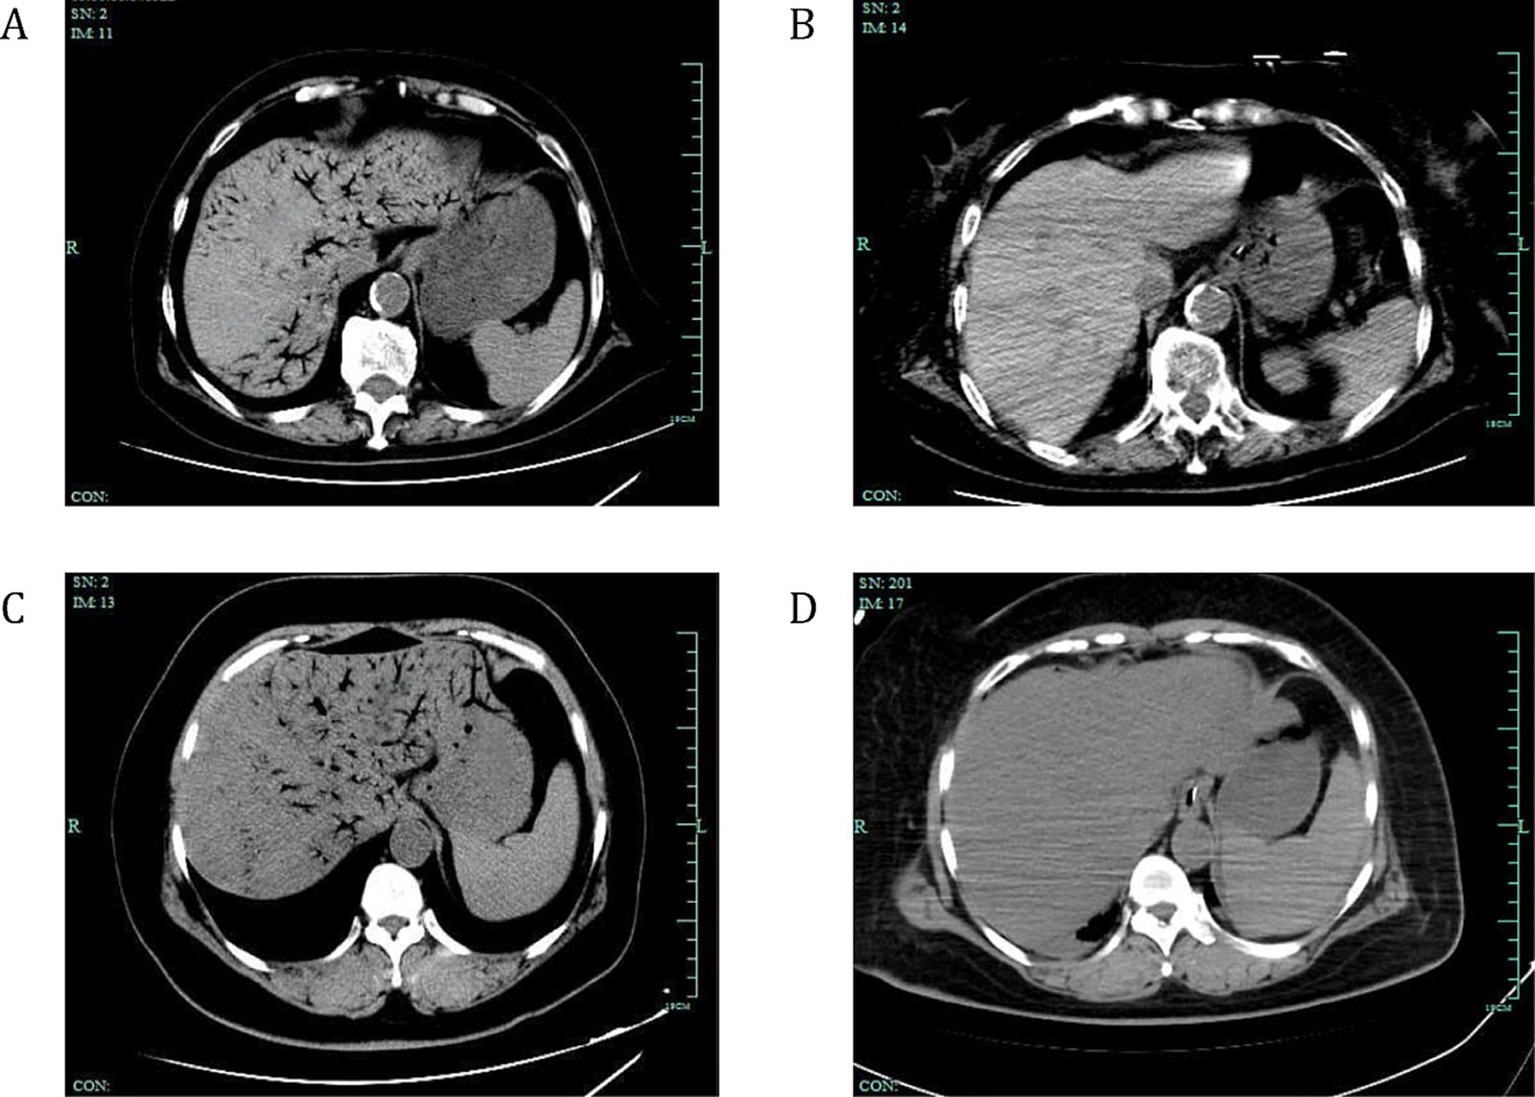

To further illustrate the treatment outcomes of patients with HPVG, Figure 2 presents the CT scans of two patients with varying degrees of HPVG before and after surgical treatment. These images show the pre- and post-surgical comparisons, as well as the changes in gas absorption. These images showed that surgical treatment significantly improved gas accumulation and recovery after surgery.

Figure 2

Changes in gas absorption before and after surgical treatment in two patients with HPVG. CT scans showing the absorption of venous gas in two surgically-treated patients with HPVG. (A) The abdominal CT scan displays extensive gas within the portal vein system and mesenteric veins. (B) Two days later, the gas dissipated. (C) Another abdominal CT scan showing extensive gas within the portal vein system and mesenteric veins. (D) One day later, the gas dissipated. White arrows indicate the presence of gas within the venous system. HPVG, hepatic portal venous gas; CT, computed tomography.